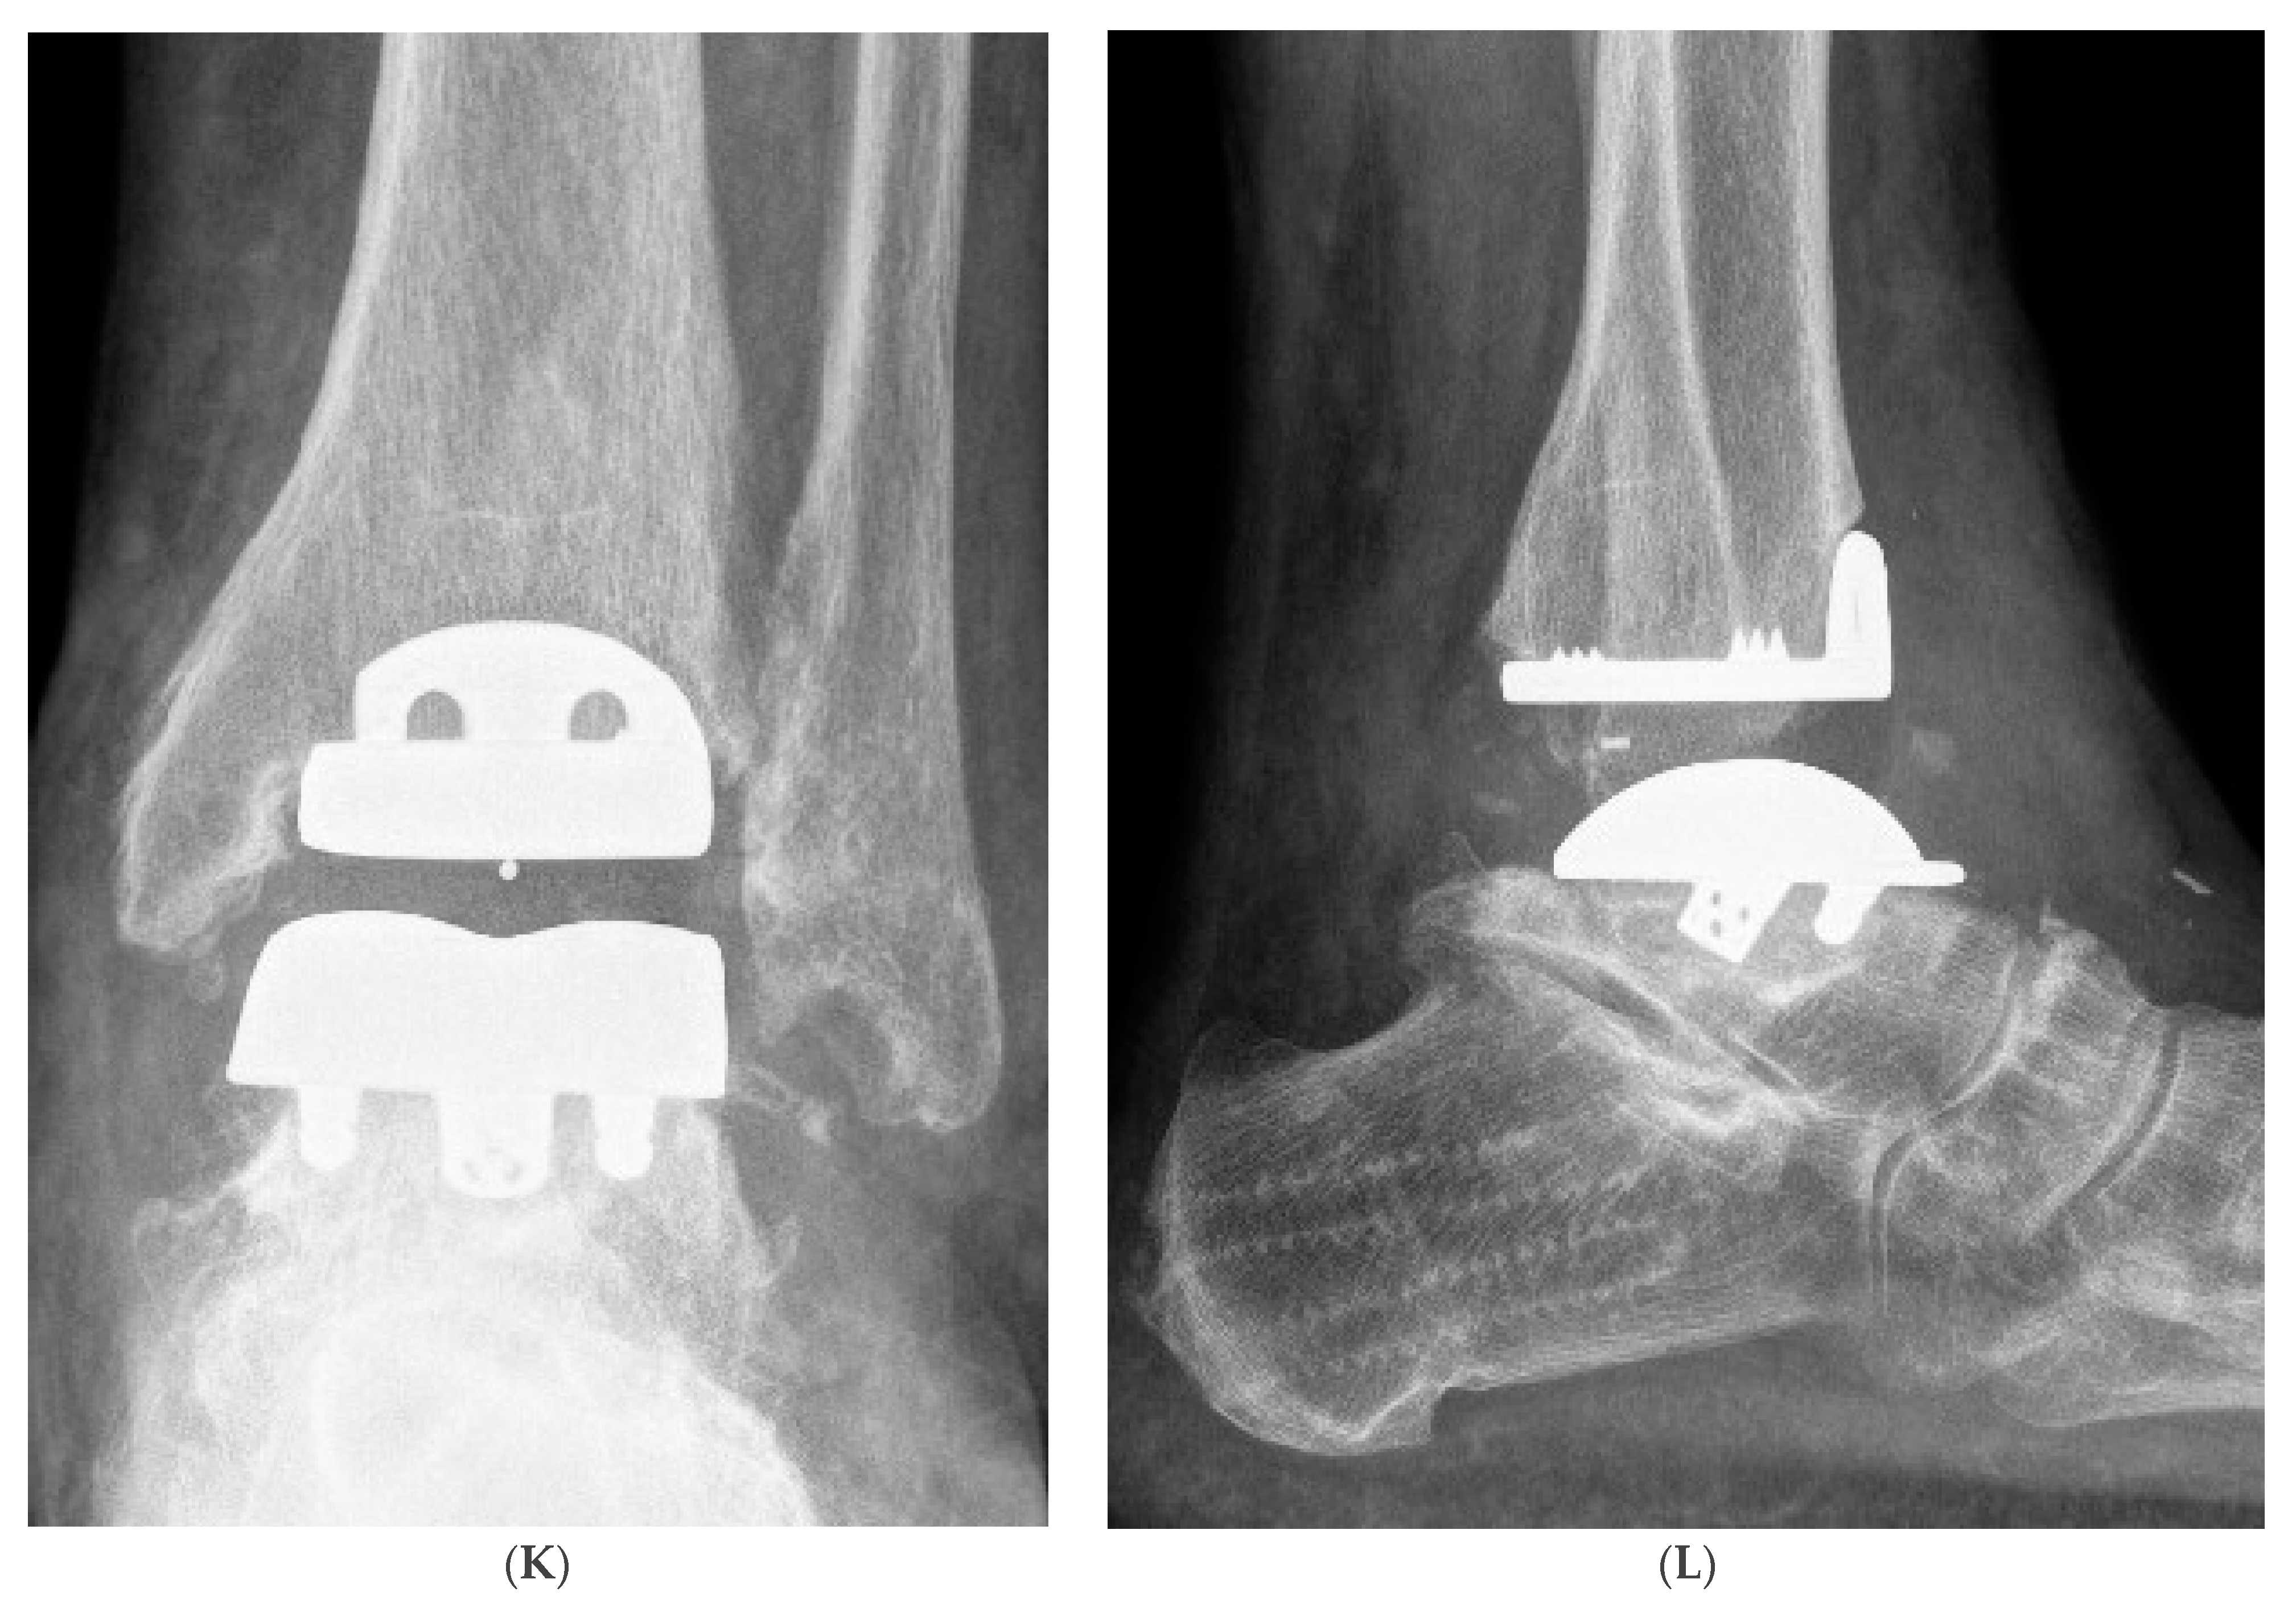

2. Materials and Methods

Surgical Procedure

3. Results